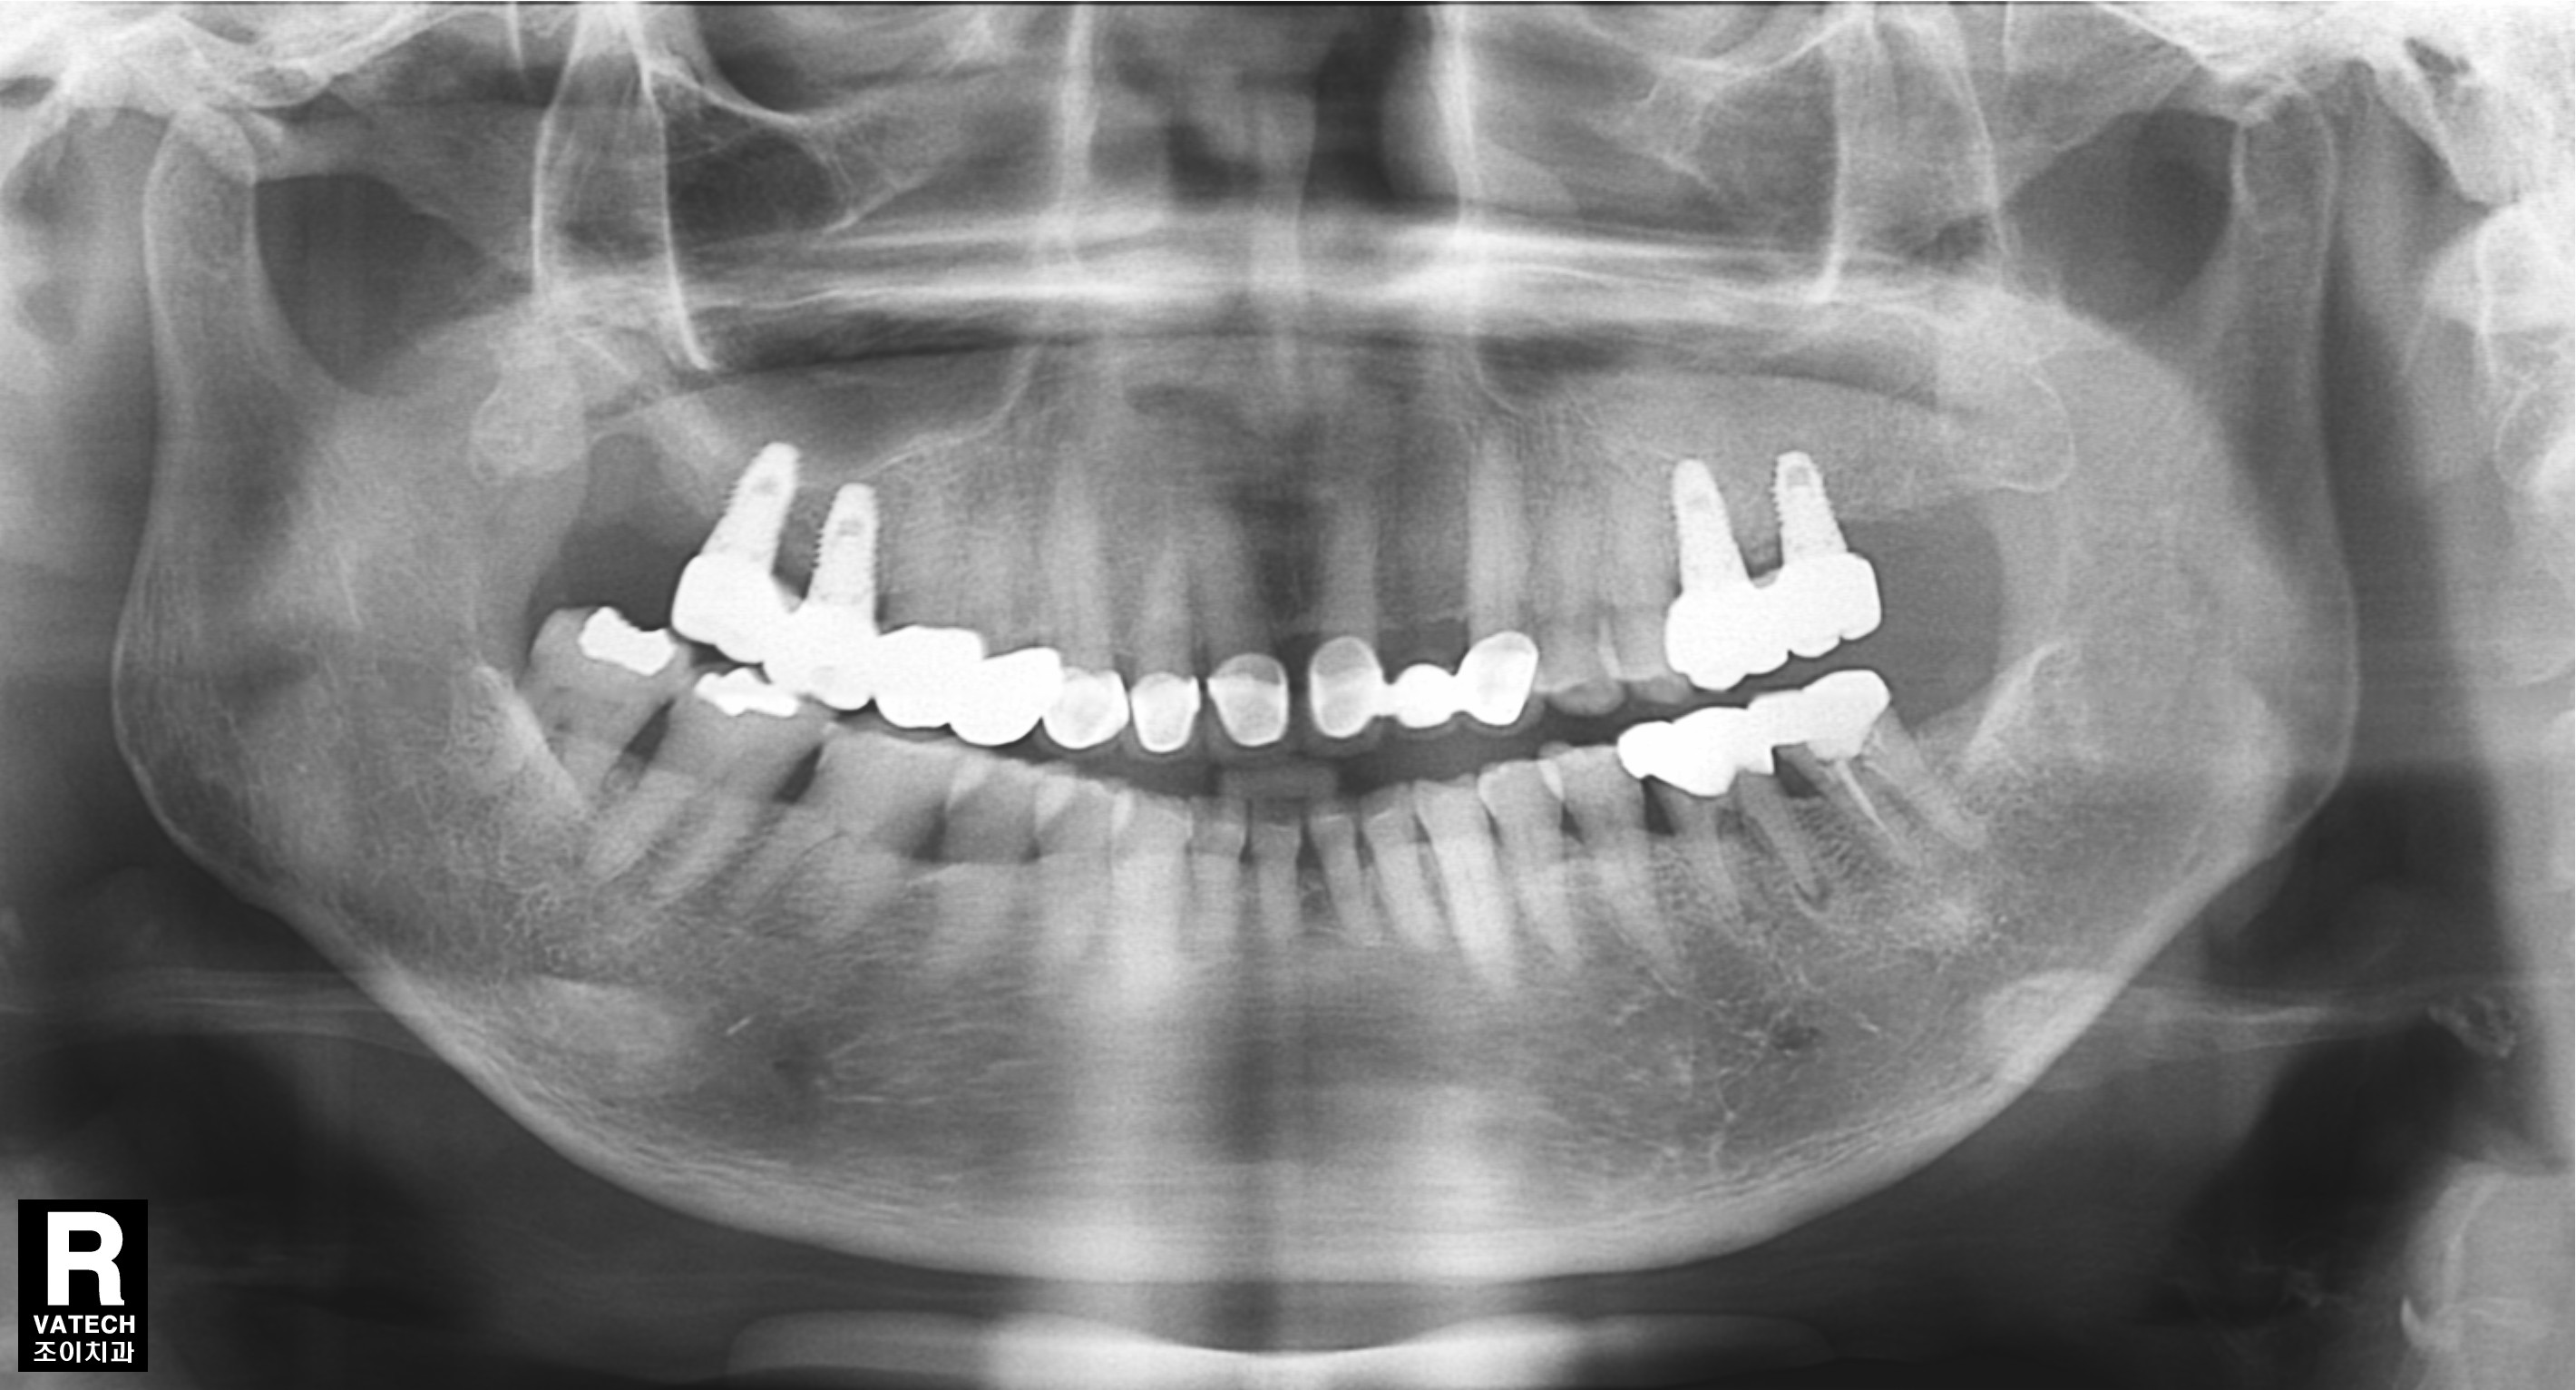

[임플란트] 제목 : 상악구치

흔히 일어나는 구치 상실의 수복 례